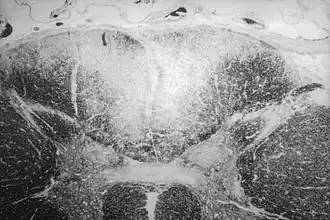

Le tabes dorsalis est une dégénérescence des cordons postérieurs (ou colonnes dorsales) de la moelle spinale observée dans la neurosyphilis. Le mot latin tabes signifie « liquéfaction, dissolution, décomposition, atrophie. »